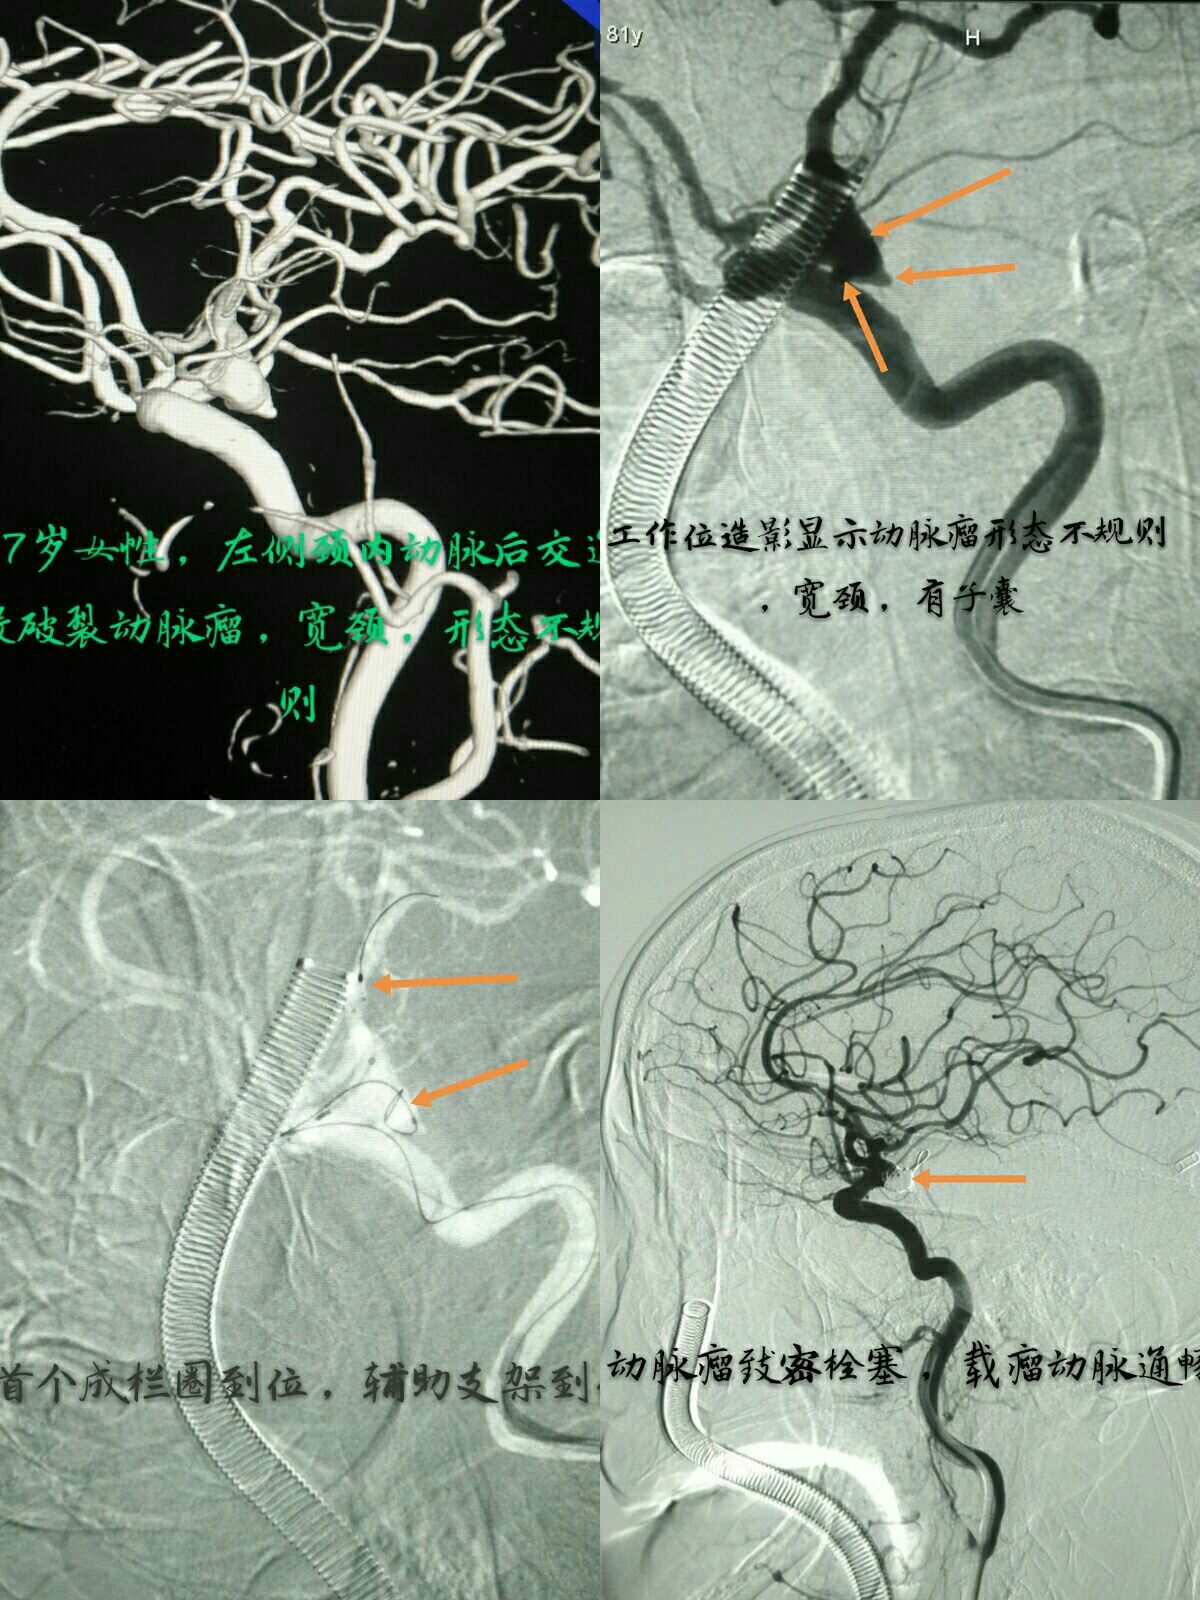

左侧颈内动脉后交通段宽颈动脉瘤,支架辅助下栓塞动脉瘤,术后后交通动脉通畅